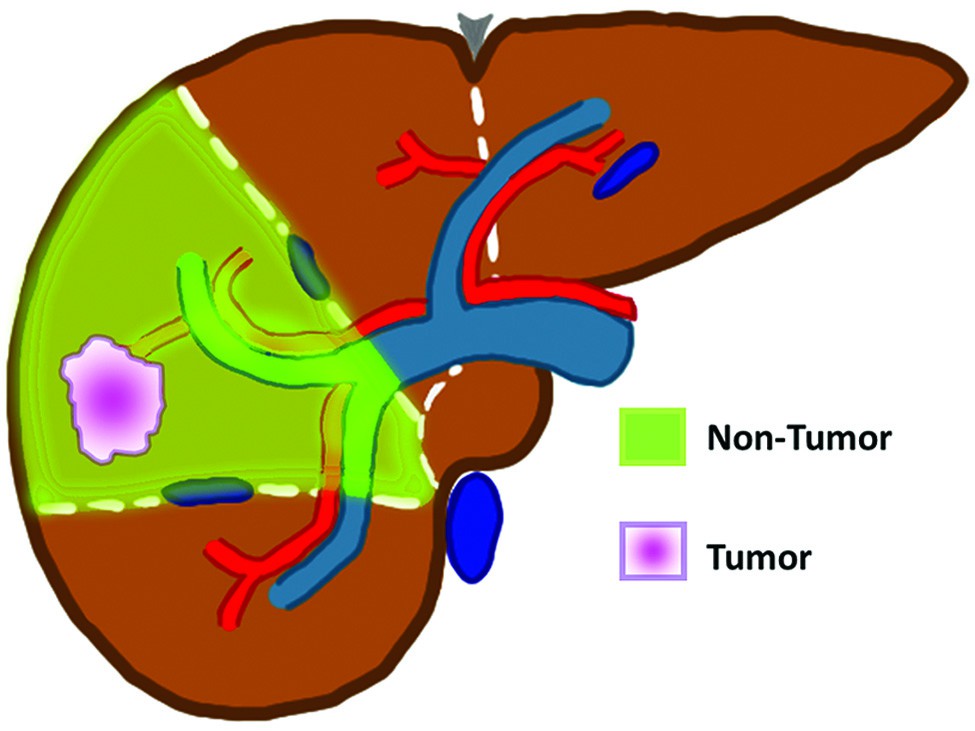

I due principali modelli dosimetrici utilizzati nella pratica clinica sono il modello MIRD (Medical Internal Radiation Dose) e il modello a partizione. La differenza concettuale fondamentale risiede nel modo in cui ciascun modello presuppone la distribuzione delle microsfere:

- modello MIRD (a compartimento singolo): considera l’area di trattamento nel fegato (l’angiosoma) come un unico compartimento. Presuppone che le microsfere di Y90 si distribuiscano in modo perfettamente omogeneo sia nel tessuto tumorale che in quello non tumorale all’interno dell’area perfusa;

- modello a Partizione (a due compartimenti): considera l’area di trattamento come composta da due compartimenti distinti: il tumore e il tessuto epatico non tumorale. Presuppone che le microsfere si distribuiscano in modo omogeneo ma con concentrazioni diverse all’interno di ciascuno di questi due compartimenti.